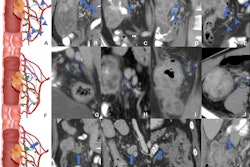

The bill would provide Medicare coverage for seniors who choose to be screened with CTC, also known as virtual colonoscopy. The exam is recommended by the American Cancer Society and has been shown to increase screening rates when it's offered. Cigna, UnitedHealthcare, Anthem Blue Cross/Blue Shield, and other major insurers cover screening virtual colonoscopy, and more than 20 states require insurers to cover these exams; however, Medicare does not cover beneficiaries for CT colonography, according to ACR.